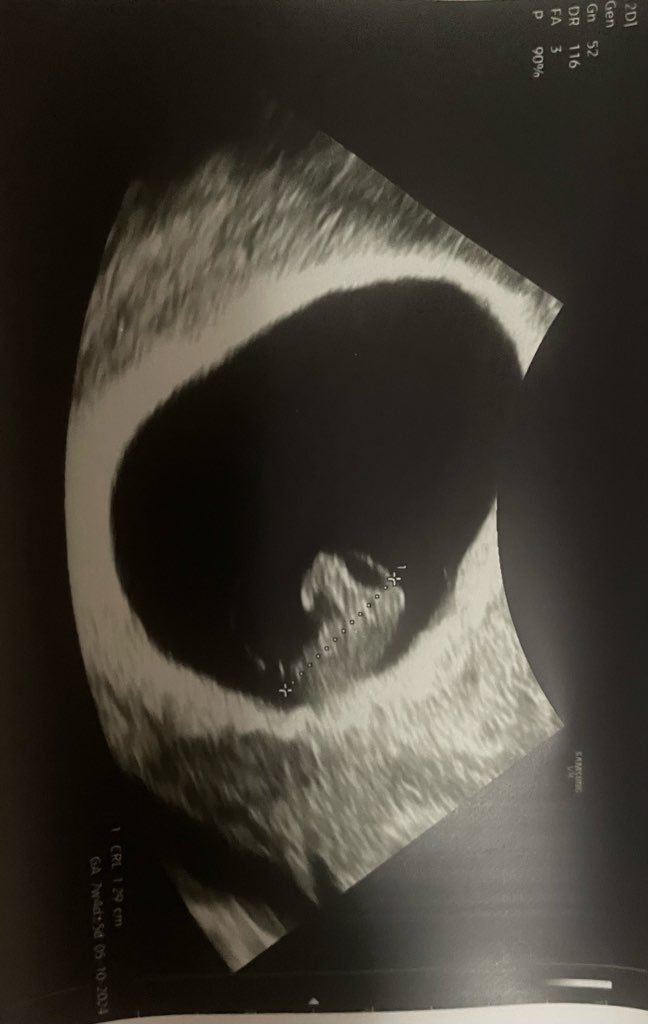

też przyjmuję te tabletki! Ratują mnie.Wróciłam od ginekologa. Przepisał mi Xonvea na mdłości. Z dzidziusiem wszystko dobrze, popłakałam się jak zobaczyłam serduszko. Bije 140. Maluszek ma 1,29 cm i wypada na usg 7+4, a mi wychodzi dziś 7+0 z OM.

Jak dojadę do domu to wyślę wam zdjęcie